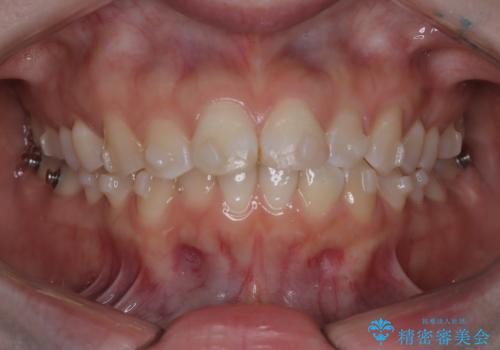

- 前歯のデコボコ(叢生)を気にされてご来院されました。精密な検査の結果、歯が並ぶスペースが不足していることが判明。患者様のご希望から、透明で目立ちにくいインビザライン(マウスピース矯正)による治療計画を立案しました。抜歯を避け、奥歯全体を奥へ動かす遠心移動という方法でスペースを確保し、前歯の叢生を解消することを目指します。

今回の矯正治療では、透明なマウスピース型の装置インビザラインを使用しました。この装置は取り外し可能で、日常生活で目立ちません。治療は、緻密に計算された計画に基づき、段階的に作製されたマウスピースを交換していくことで、奥歯から順に全体を後方へ移動させる遠心移動を実施。これにより、前歯を並べるための十分なスペースが確保され、デコボコが解消されました。抜歯することなく、機能的にも審美的にも整った美しい歯並びを獲得していただけました。